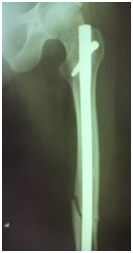

We report a case of bilateral femoral fracture in a patient after 7 years of treatment with alendronate at a dose of 70 mg weekly. The patient was a 67 y.o. female with no history of any comorbidity such as diabetes, alcohol abuse, smoking, chronic use of glucocorticoids or others. She fell from her own height in March 2014, resulting in a transverse femoral shaft fracture of the left femur (Figure 1A), treated with a blocked anterograde intramedullary nail (Figure 1B & 1C). In June 2016, she suffered a contralateral short oblique femoral fracture with no history of direct trauma, presumably with a torsional mechanism - rotation around the body axis (Figure 2A). The treatment of choice was also a blocked anterograde intramedullary nail (Figures 2B & 2C). We can observe in Figures 1 & 2 the absence of compromised trabecular bone or thinning of cortical bone, corroborating the probable pathophysiology behind bisphosphonate-associated fractures - decreased bone remodelling - and not osteopenia/osteoporosis.

Figure 1A Left femoral anteroposterior radiograph - Simple short oblique tract fracture with cortical thickening. 1B & 1C Postoperative radiograph – anterograde blocked nail left femur.

Figure 2A Right femoral anteroposterior radiograph – Simple short oblique tract fracture with cortical thickening. 2B & 2C Postoperative radiography – anterograde blocked nail right femur.